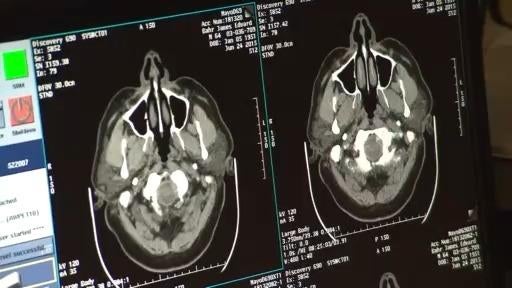

Health expert breaks down why Alzheimer's Disease numbers are high in the U.S.

Dr. Kavita Desai joins CBS News Colorado to break down Alzheimer's Disease numbers are high in the U.S.